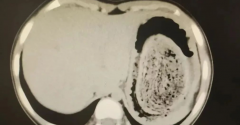

胃石

• 一天几个柿子下肚,2枚3厘米结石堵在胃里

胃石 柿子 单宁 2024/10/28